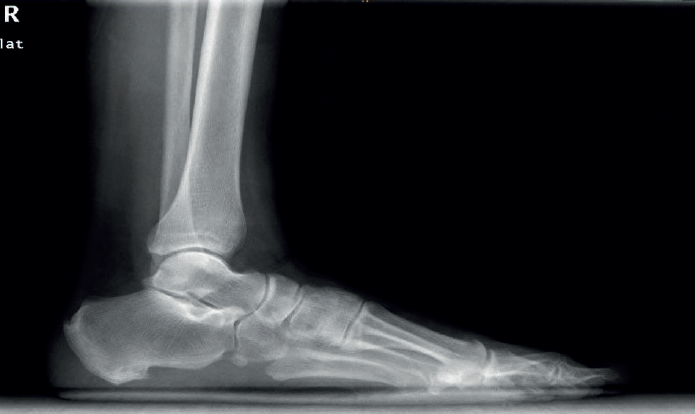

Diagnóstico por imagen

El estudio radiológico se debe realizar de ambas extremidades y en carga, para poder valorar desaxaciones (en varo o valgo) y asimetrías. En la proyección anteroposterior de tobillos se puede observar si existe un arrancamiento de la pared lateral del maléolo peroneal que indica una avulsión del RPS (signo indirecto de luxación conocido como fleck sign). En el perfil podemos valorar la presencia de un OP (Figura 4). La proyección oblicua puede mostrar un tubérculo peroneal hipertrófico a nivel de la pared lateral del calcáneo.